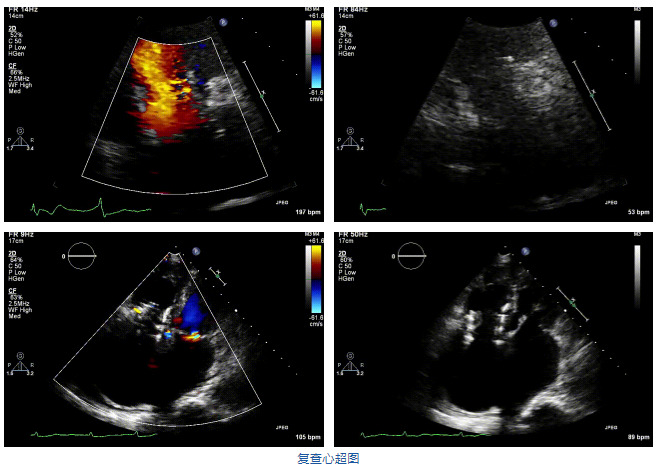

2021年12月7日,復(fù)旦大學(xué)附屬中山醫(yī)院葛均波院士團(tuán)隊完成的首批兩例LuX-Valve Plus經(jīng)血管三尖瓣置換患者順利出院,從患者入院至出院僅歷時一周時間,出院時患者狀態(tài)恢復(fù)良好,復(fù)查心超三尖瓣無反流。

結(jié)合術(shù)前CT評估結(jié)果,葛均波院士團(tuán)隊最終決定選用LuX-Valve Plus 50mm和55mm兩種型號的瓣膜,并于2021年11月30日順利完成LuX-Valve Plus經(jīng)血管三尖瓣置換術(shù),手術(shù)室即刻拔除氣管插管,術(shù)后第二天轉(zhuǎn)出心內(nèi)科監(jiān)護(hù)室,下床活動。術(shù)后患者三尖瓣反流癥狀得到顯著改善,復(fù)查心超結(jié)果顯示人工三尖瓣瓣膜支架固定穩(wěn)定,瓣葉關(guān)閉形態(tài)未見異常,未見明顯反流。

在本次救治性臨床研究中,治療的兩例患者病因不同,解剖結(jié)構(gòu)復(fù)雜,均為極重度三尖瓣反流,手術(shù)最終都順利植入了LuX-Valve Plus三尖瓣人工瓣膜。術(shù)后超聲顯示瓣膜支架固定穩(wěn)定,反流癥狀顯著改善,取得了良好臨床治療效果。